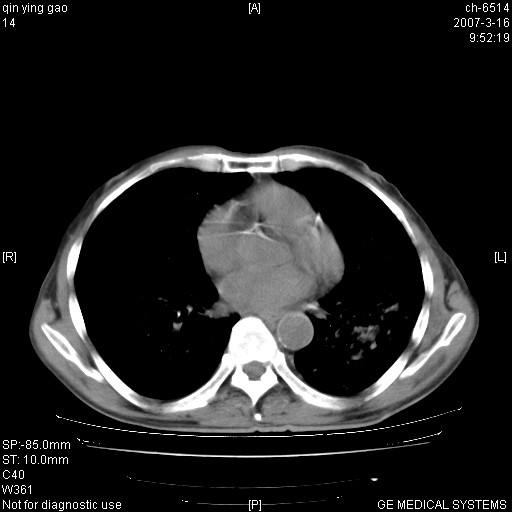

男,64岁.乏力2个月,畏寒、发热1月余。体重下降。血沉加快,白细胞不高。

双肺以中上肺野为著斑片状.结节壮密度增高影 左上肺前段可见小类圆钙化灶 纵隔淋巴结无明显肿大

3.主动脉弓.冠状动脉钙化形成

双肺以中上肺野为著斑片状.结节壮密度增高影,纵隔淋巴结无明显肿大。考虑:

1、肺结核。

2、主动脉、冠状动脉硬化。

病变以两肺上野为著,部分病灶有钙化,纵隔窗显示病灶有新老不一,这个首先和结核脱不了干系,还有部分病灶有融洽的倾向,肿瘤也不能完全排出